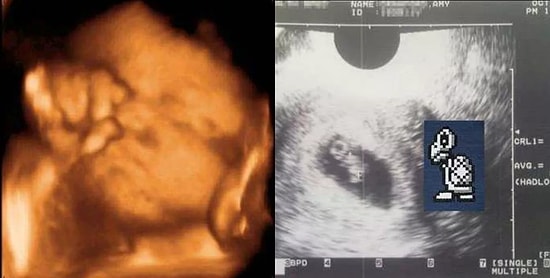

Криповые изображения, которые точно не ожидаешь увидеть на снимках с УЗИ

Есть подружка или жена, чьи биологические часы начали биться в ритме колыбельной? Или, может, вы хотите показать одному из своих друзей, во что он ввязывается, если хочет броситься с головой в размножение? Больше ничего не нужно искать, ведь есть эти криповые снимки с УЗИ!Так что не важно, хотите ли вы показать своей второй половинке, на что на самом деле похожа беременность, или хотите убедиться в этом сами, эти картинки вам точно помогут. Кто знает, может, окажется, что все гораздо веселее, чем вы предполагали.